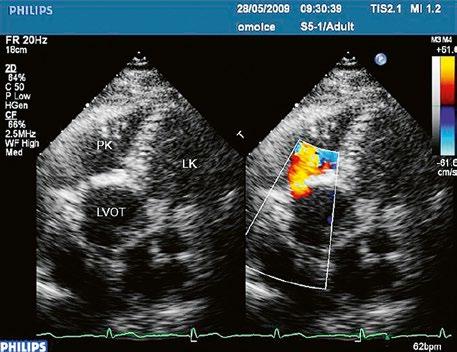

z Defekt síňového septa typu secundum: 70 % všech komunikací na úrovni síní, v místě fossa ovalis, s možnou extenzí ke stěnám levé síně (Obr. 45.1, Obr. 45.2, Video 45.1, Video 45.2).

z Defekt síňového septa typu sinus venosus superior: 9 %, v místě vústění horní duté žíly (HDŽ), která na defekt nasedá, téměř vždy je spojen s parciálním anomálním návratem pravostranných plicních žil do HDŽ nebo do pravé síně (kap. 45.18 Anomální návrat plicních žil (Obr. 45.3, Obr. 45.4, Video 45.3, Video 45.4).

Obr. 45.2 Defekt septa síní typu II v TEE

AO – aorta, ASD – defekt septa síní typu secundum označen šipkou, zelenými křížky je označen malý přední rim k aortě, LS – levá síň, PS – pravá síň

Obr. 45.3 Defekt septa síní typu sinus venosus superior, TEE nad úrovní aortální chlopně, defekt je v horní části septa označen křížky

AO – aorta, LS – levá síň, PS – pravá síň

Obr. 45.4 Defekt typu sinus venosus superior s levopravým zkratem v barevném dopplerovském mapování. TEE v longitudinální projekci, defekt se nachází v horní části septa, je označen žlutou šipkou, na něj nasedá horní dutá žíla (HDŽ)

AP – plicnice, LS – levá síň, PS – pravá síň

Poslechový nález systolického šelestu nad plicnicí s fixním rozštěpem 2. ozvy je nenápadný. Echokardiograficky je patrná dilatovaná a objemově přetížená pravá komora s paradoxním pohybem septa (Obr. 45.9), zkratový tok může být vidět i transtorakálně (TTE) (Obr. 45.10, Video 45.3, Video 45.7), ale suverénní diagnostickou metodou je jícnová echokardiografie (TEE), případně s 3DE zobrazením (Obr. 45.1, Obr. 45.2,

Obr. 45.4, Video 45.1, Video 45.2, Video 45.8), která určí nejen velikost a tvar defektu, ale i vhodnost katetrizačního uzávěru.